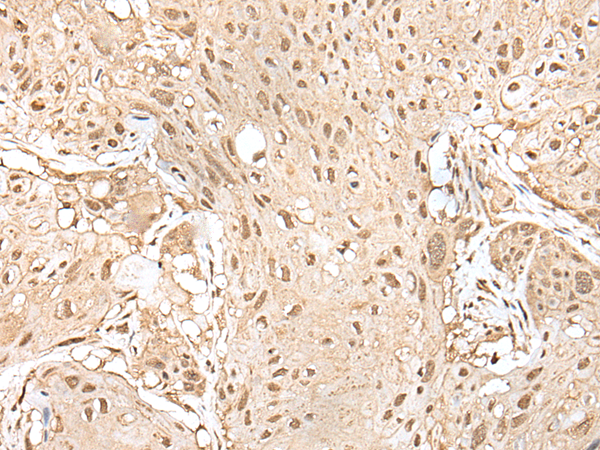

ELISA, WB, IHC

IHC positive control:

Human esophagus cancer and human brain

IHC Recommend dilution:

25-100